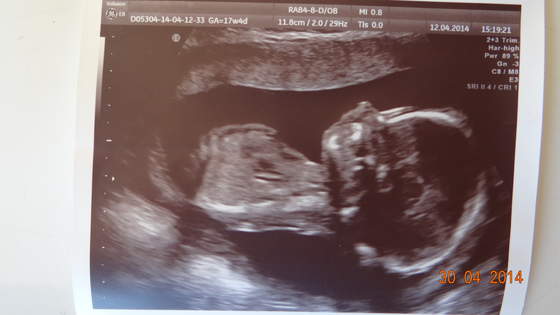

Jak to zazwyczaj bywa doktor powiadomil o badaniach prenatalnych - mam na mysli test podwojny z krwi + usg diadnostyczne (kosc nosowa i przeziernosc karkowa). W pierwszym tescie, usg bylo robione na wizycie kontrolnej i wyszlo ok a na tescie z krwi wyszlo prawdopodobienstwo zespolu downa 1:145 (dodam ze mam 23 lata!) telefon z przychodni.. szok.. Moj doktor postanowil ze powtorzymy badanie w szpitalu zeby skumulowac wyniki krwi i usg. I wyszlo juz lepiej chociaz i tak niezbyt niskie ryzyko bo 1:370. Wskazania do amnio sa od 1:300 ale pani genetyk stwierdzila ze wypisze skierowanie na wszelki wypadek i pozostawi do wlasnej decyzji chociaz zdecydowanych wskazan nie widzi.. tak jak wspomnialam nie zdecydowalismy sie na amniopunkcje. ale na usg plodu w 20-23 tc tak, aby przekonac sie w 100% ze nasz synek jest zdrowy

nie ma widocznych wad serca wiec wykluczamy tez ZD przy ktorym jak wiadomo czesto wystepuja wady wrodzone, nosek tez ma pieknie widoczny, duzy.. smieje sie ze po tatusiu

Synus jest bardzo ruchliwy i buntowniczy na badaniu pani doktor az sie na niego zdenerwowala